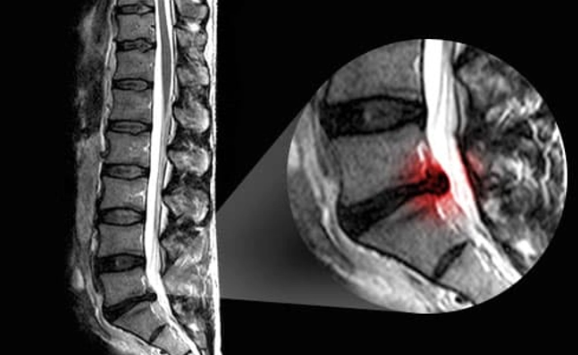

Bác sĩ cũng sẽ yêu cầu chụp MRI để có thêm thông tin về vị trí và nguyên nhân khiến dây thần kinh bị kích thích. MRI cho thấy sự liên kết của đĩa đệm đốt sống, dây chằng và cơ. Chụp CT sử dụng thuốc nhuộm tương phản cũng cung cấp hình ảnh hữu ích về tủy sống và dây thần kinh. Xác định nguyên nhân gây đau thần kinh tọa sẽ giúp hướng dẫn quá trình điều trị.

Chụp X-quang giúp xác định các bất thường về xương nhưng không thể phát hiện các vấn đề về thần kinh.

Có nhiều xét nghiệm hình ảnh để chẩn đoán đau thần kinh tọa